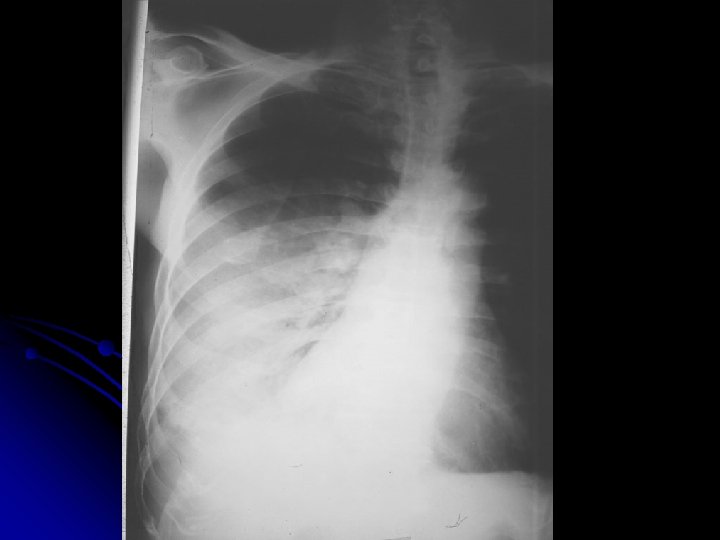

TB l 51 yaşında, işçi l Erkek l Doğum yeri: Zonguldak l

l ŞİKAYETİ Öksürük Koyu renkli balgam Efor dispnesi

l FİZİK MUAYENE: siyanoze, dispneik çomak parmak mevcut DSS: 26 (torako abdominal) OSKÜLTASYONDA bilateral inspiratuvar raller TA: 130/80 Nb: 86/dk

FVC % 55 l FEV 1/FVC %82 l Pa 02 50 mm. Hg l Pa CO 2 38 mm. Hg l

TANI ? ? ?